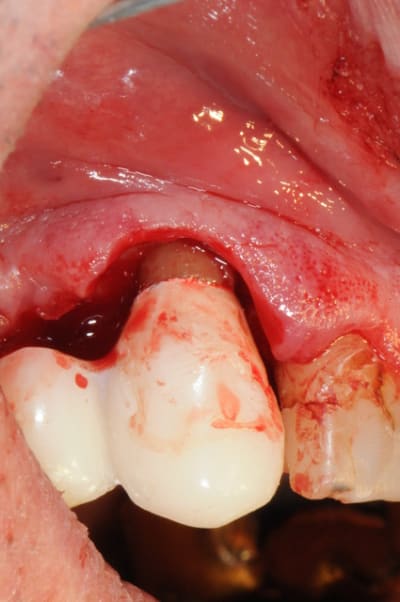

sinon, voici le protocole pour une élongation coronaire.

(c'est juste un petit cas clinique, pas La solution)

laisser au moins deux mois après la chirurgie avant d'attaquer la prothèse définitive.

oups , il manque les photos..

petite critique ; j'aurai aussi pu déplacer apicalement la gencive attachée...

effectivement,limite pour le déplacement apical...mais sympa;

mais beaucoup plus difficile à gérer esthétiquement lorsque il y a des dents en mésial et distal ;on créer une dénudation radiculaire des dents voisines avec risque de sensibilité et esthétique discutable par disparition de la papille,il n'est pas toujours simple de prendre la décision.